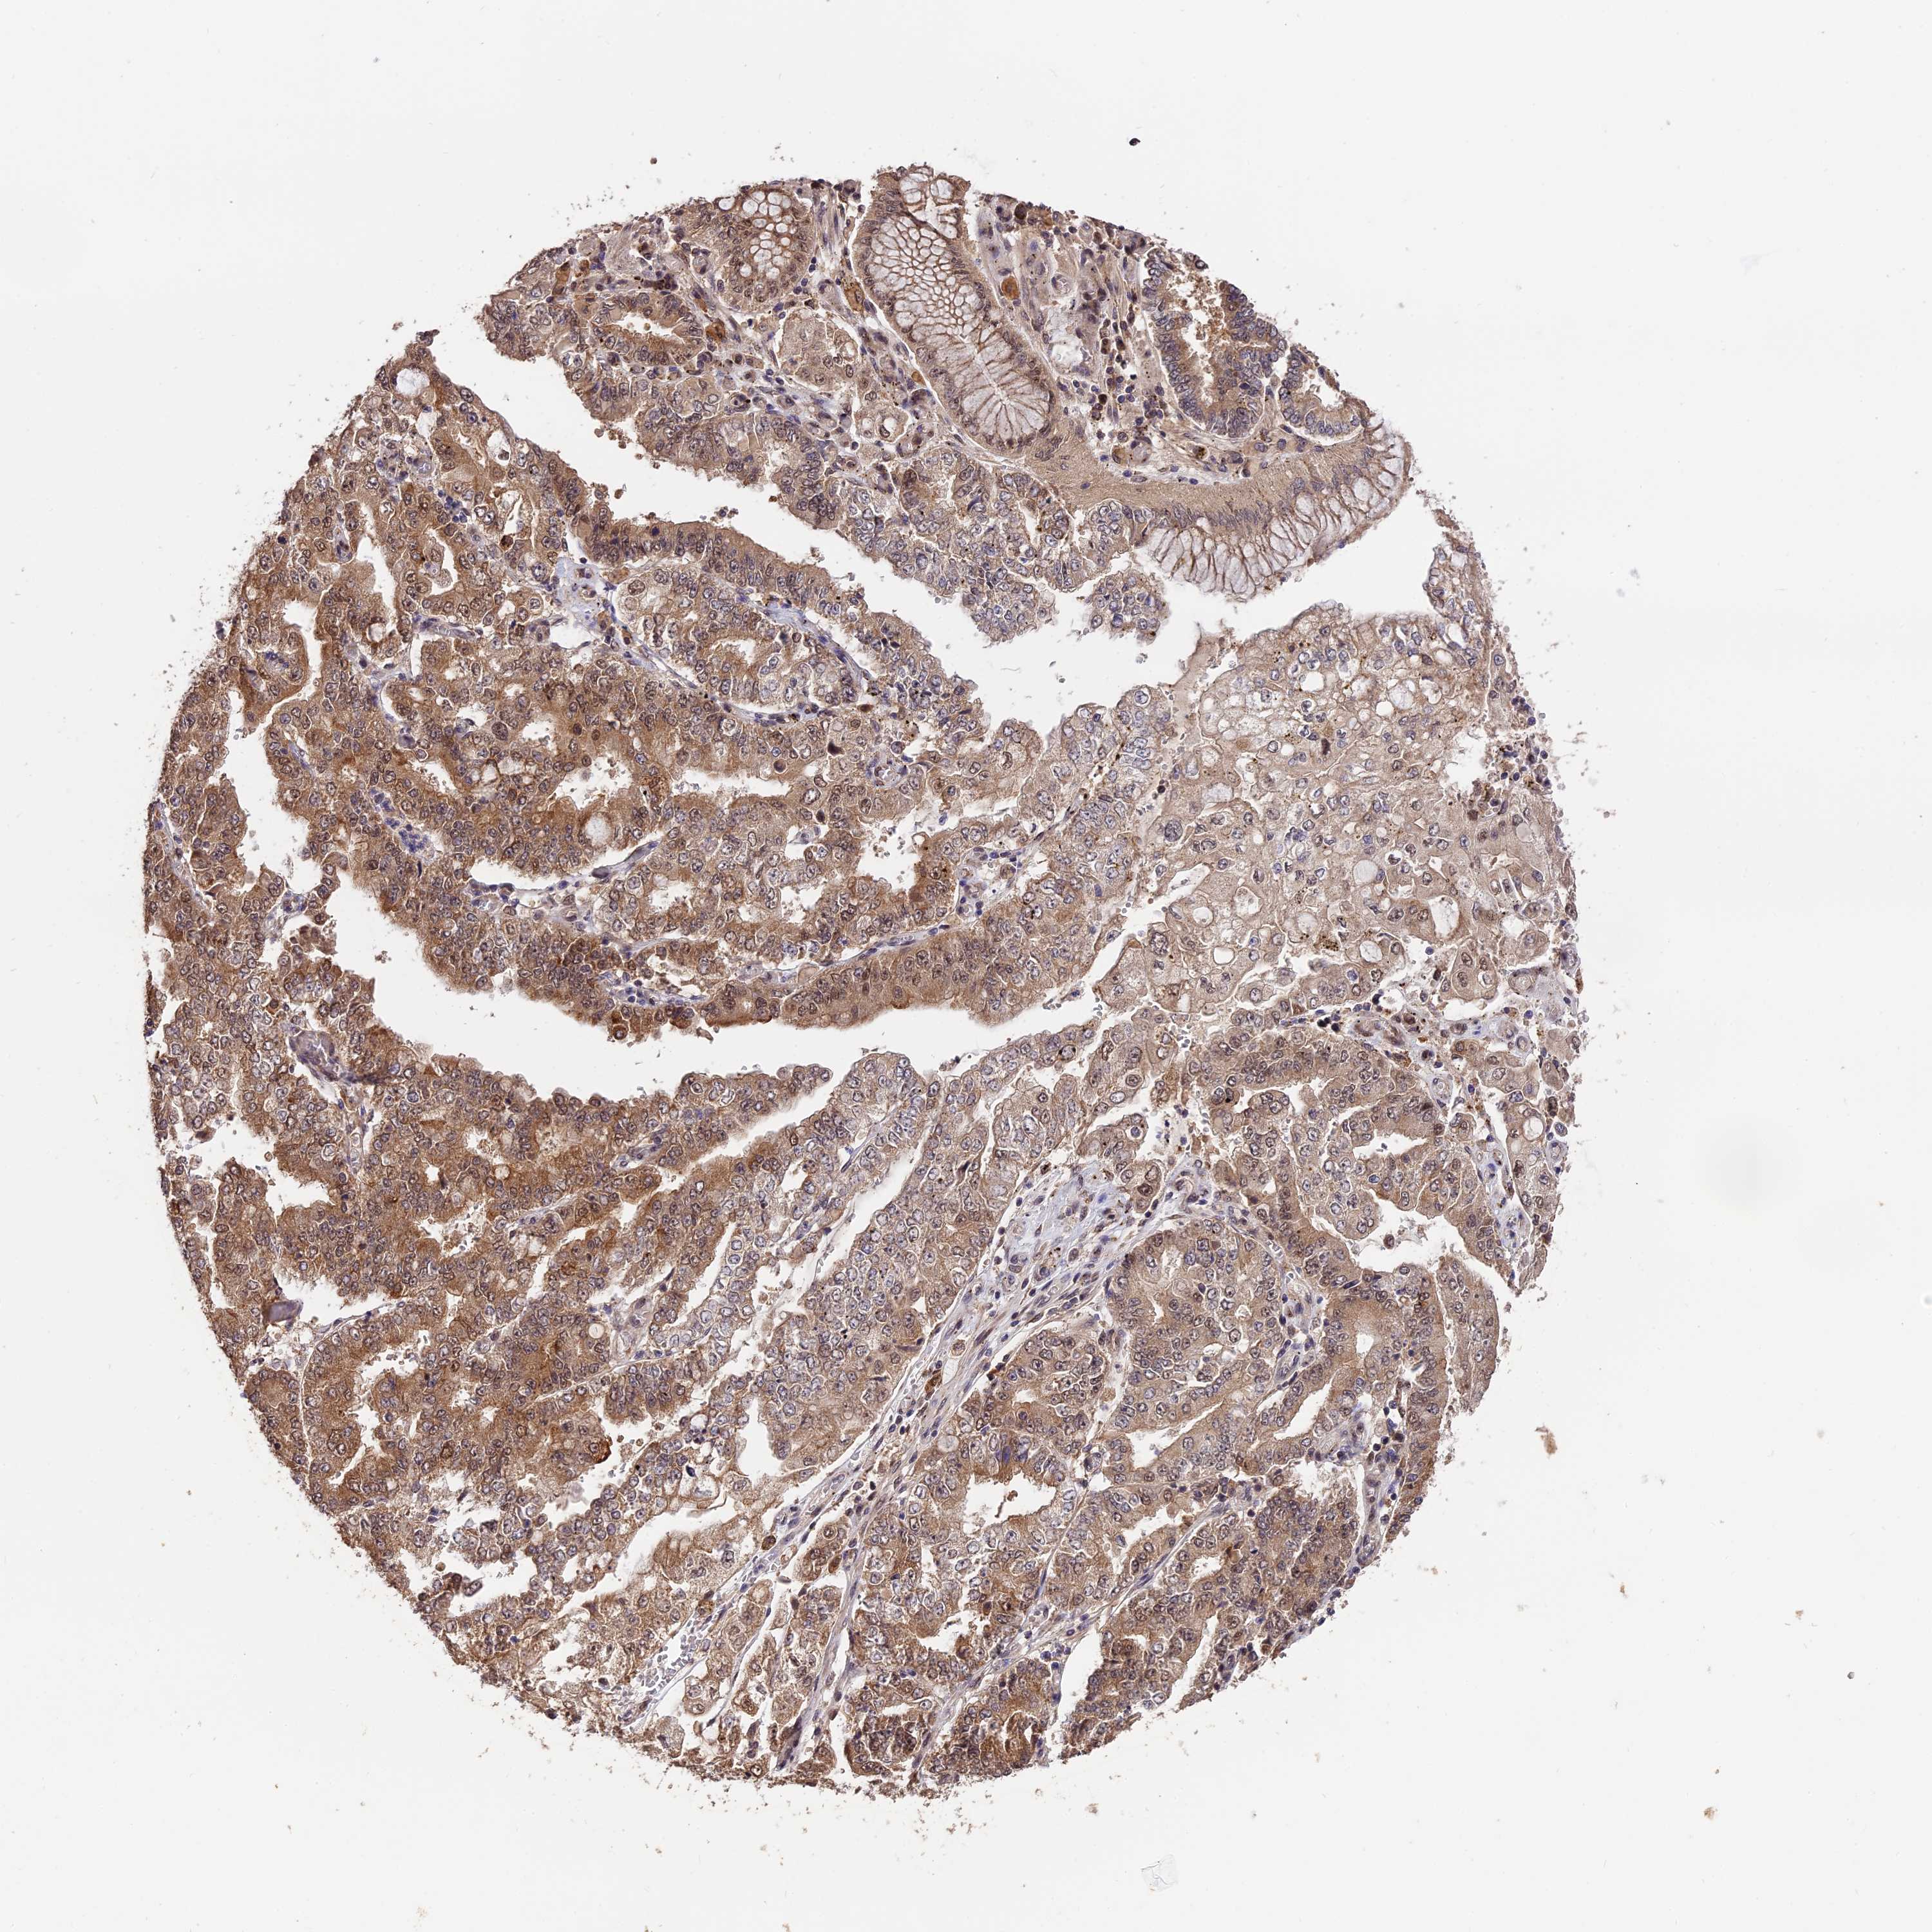

STOMACH CANCER - Protein expressioni

A mouse-over function shows sample information and annotation data. Click on an image to view it in a full screen mode. Samples can be filtered based on level of antibody staining by selecting one or several of the following categories: high, medium, low and not detected. The assay and annotation is described here.

Note that samples used for immunohistochemistry by the Human Protein Atlas do not correspond to samples in the TCGA dataset.

Antibody stainingi

Antibody staining in the annotated cell types in the current human tissue is reported as not detected, low, medium, or high, based on conventional immunohistochemistry profiling in selected tissues. This score is based on the combination of the staining intensity and fraction of stained cells.

Each image is clickable and will lead to virtual microscopy that enables deeper exploration of all samples and also displays staining intensity scores, fraction scores and subcellular localization as well as patient and tissue information for each sample.

Antibody HPA041130

Antibody HPA041380

Staining

High

Medium

Low

Not detected

Intensity

Strong

Moderate

Weak

Negative

Quantity

>75%

75%-25%

<25%

None

Location

Nuclear

Cytoplasmic/membranous

Cytoplasmic/membranous,nuclear

Adenocarcinoma, NOS